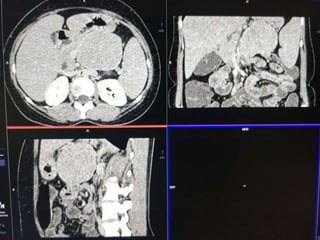

CECT ABDOMEN

CASE1

DIFFERENTIALS

1. Neurogenic tumor possibly neurofibroma

• Age of presentation

• Well defined hypodense solid lesion

• Mild homogeneous enhancement

• Points against: Beak sign with pancreas

2. Pancreatic neuroendocrine tumor

• May present as hypoenhancing mass rarely

• Points against: Age, clinical presentatation and enhancement

characteristics

Most likely diagnosis-

Retroperitoneal Neurogenic Tumor possibly

Neurofibroma